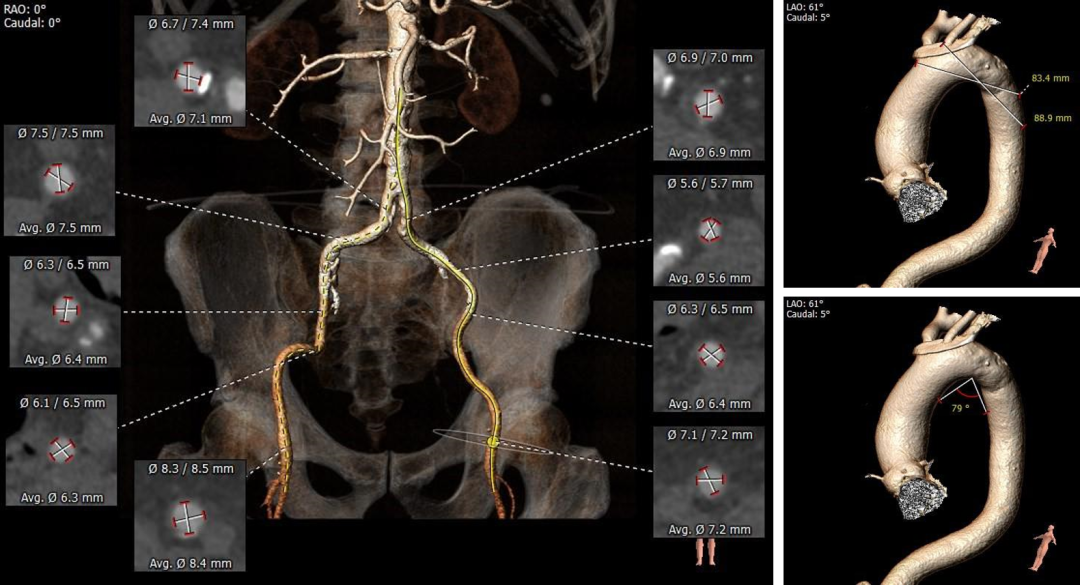

• 瓣环水平夹角为58°,右侧髂总动脉条状钙化,入路血管管径良好。

外周血管及主动脉弓解剖